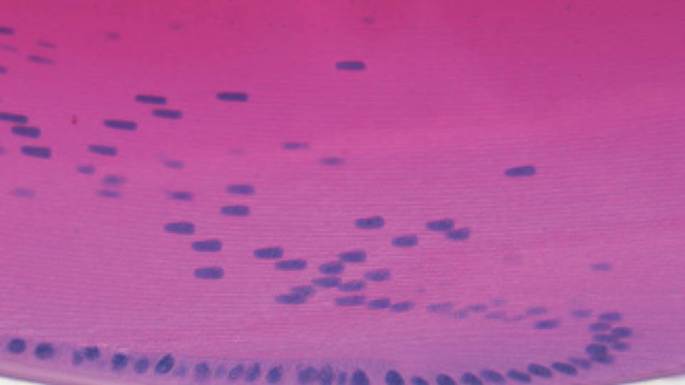

En 1833 David Brewster determino que el lente de bacalao tiene una estructura calculada que contene 5 millones de células de fibra, cada una 4.8 milímetros de largo, usando sólo una vela y una barra de acero finamente diseñada. Posteriormente hubo estudios sobre la embriologia , bioquimica en relacion al la estructura proteica del cristalino. Luego se determino que cromosoma no sexual estaba asociado a la suseptibilidad de las cataratas. Los mensajeros de ARN que codificaban a δ-crystallinas, fuero clonados y estudiados, estas proteinas cumplen la función en el lente del ojo en transmitir la luz y enfocarla en la retina. Los lentes logra a través de un único tipo de célula que sigue un desarrollo o patrón, comenzando como un miembro de la zona germinativa en una capa única de células epiteliales anterires en superposición de una masa de células de las fibras. Las células epiteliales luegomigrar lateralmente hacia el ecuador del cristalino,donde se alargan y se inverte para formar células de las fibras secundarias, dispuestas en una curva,en forma de configuración de cebolla . Al hacer esto, las células sintetizan grandes cantidades de proteínas cristalinas,de tal manera que contienen tal vez la más alta concentración de proteínas que se encuentran en cualquier otro tejido.También se degradan orgánelos, ya que minimizan el espacio extracelular y aumentan la densidad de sus membranas celulares a niveles cercanos al del citoplasma de la célula, todos los cuales disminyen dispersando la luz. Por lo tanto, la transparencia se lleva a cabo principalmente a través de una combinaciónde la microarquitectura de la lente y en un nivel molecular, la lente densamente poblada de cristalinas. Estas Cristalinas son extremadamente estables, altamente ordenadas y proporcionan relativamente un constante índice de refracción, lo que permite la transparencia de la lente.

Debido a que células de que generan las fibras ópticas ya diferenciadas carecen del aparato de síntesis para producir nuevas proteínas, las cristalinas no vuelven y las que están en el centro de la lente se encuentran entre las proteínas más antiguas en el cuerpo. La conservación es crucial, para la estructura y función de las cristalinas, asi la prevención de la opacidad del cristalino. Otra de las actividades biológicas de la lente sirven principalmente para proteger los sistemas complementarios de

embalaje cristalina y la disposición de células de fibra frente a perturbaciones y daños por edad y injuria externas, especialmente por la luz ultravioleta, del estrés oxidativo y glicación.

Los cambios estructurales catastróficos en cristalinas se ha visto en muchos cataratas hereditarias, pueden abrumar a los sistemas defensivos del lente y también podría ser refractaria a la actividad solubilizante de lanosterol identificado por los autores Zhao y otros.

Sin embargo, este agente podría ser terapéuticamente aplicable a la desnaturalización progresiva lenta de cristalinas se ve en las cataratas relacionadas con la edad. En las cataratas relacionadas con la edad , se dañan βγ-cristalinas que son

proteínas que están obligadas por alfa-cristalinas, a actúar como chaperones – proteínas

que ayudan al plegar o desplegar otras proteínas a excepción de que, en lugar de replegamiento la desnaturalizacion de βγ-cristalinas, alfa-cristalinas se solubilizan, reduciendo de ese modo dispersión de la luz. Sin embargo, como más cristalinas están dañados y atadas, los complejos de proteína a sí mismos son lo suficientemente grandes como para dispersar la luz finalmente, los complejos precipitan y la formación de la fracción de proteína insoluble (Alto peso molecular, denominados agregados) que aumenta con el envejecimiento normal y especialmente en lentes con cataratas. Estas se identifican cataratas, al menos en algunos casos, como una enfermedad proteínas de mal plegamiento. Zhao y colaboradores muestran que gotas para los ojos que contienen lanosterol son un éxito de tratamiento de las cataratas naturales en los perros. El potencial